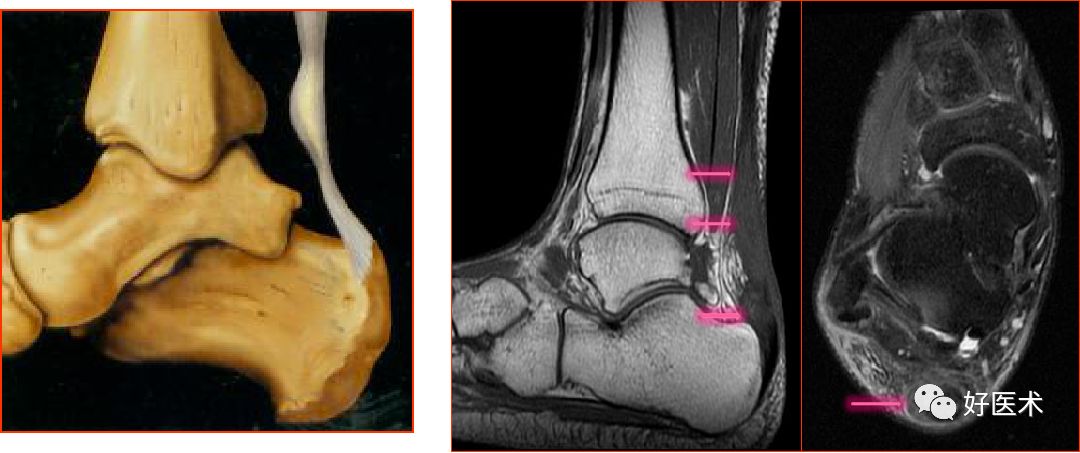

距腓前韧带

距腓前韧带撕裂

距腓后韧带

距腓后韧带部分撕裂

跟腓韧带

跟腓韧带急性完全撕裂